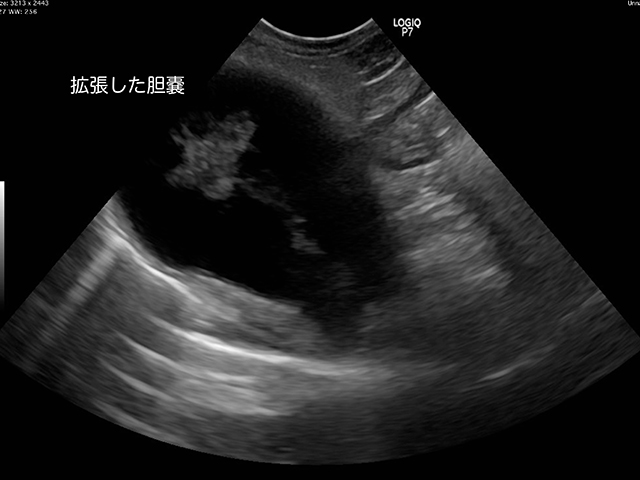

何度も吐いてしまい、ぐったりしてきたとのことで来院されたチワワさんです。

検査の結果、胆嚢が破裂していることがわかりました。

胆嚢は破れてお腹の中にゼリー状の胆汁がみられ、強い腹膜炎も起こしていました。